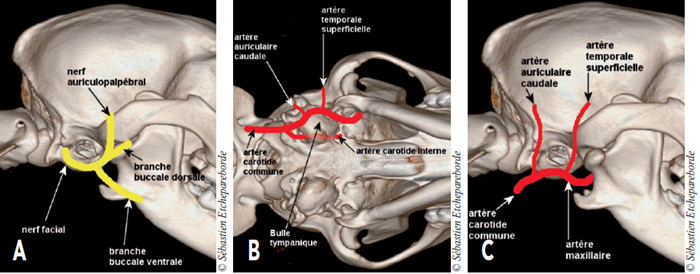

On parvient à isoler la membrane du kyste qui est ensuite disséquée jusqu’à la bulle tympanique (Photo 6). Durant la dissection, il est impératif de rester aussi près que possible de la membrane pour éviter de sectionner le nerf facial et les vaisseaux entourant la bulle tympanique (schémas A à C).

Schéma A -

Le nerf facial sort de la boite crânienne par le foramen stylomastoïdien, juste caudalement à la bulle tympanique. Ses branches se ramifient cranialement pour innerver la face.

Schéma B - Vue ventrale de la boite crânienne, rostral à droite. L’artère carotide interne passe contre la bulle tympanique, médialement.

Schéma C - Vue latérale de la boite crânienne. La bulle tympanique est entourée de vaisseaux sanguins qu’il faut prendre soin de ne pas léser.